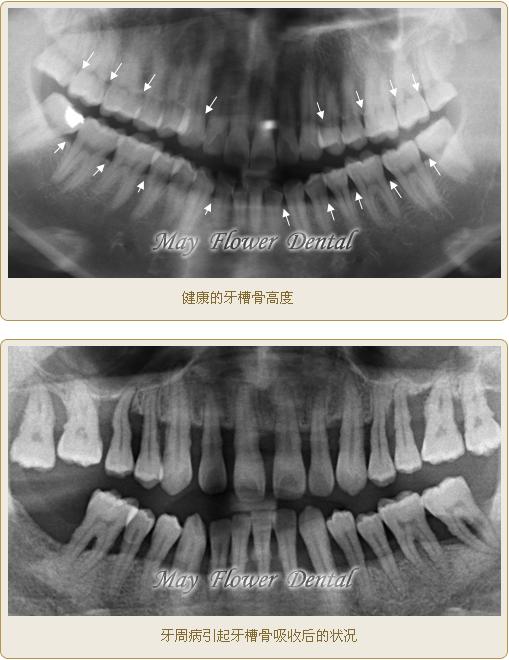

這是全口曲面斷層X(jué)光片,俗稱骷髏片,上下兩張圖片對(duì)比可以發(fā)現(xiàn)牙槽骨被吸收的情況

健康和非健康的牙齦對(duì)比